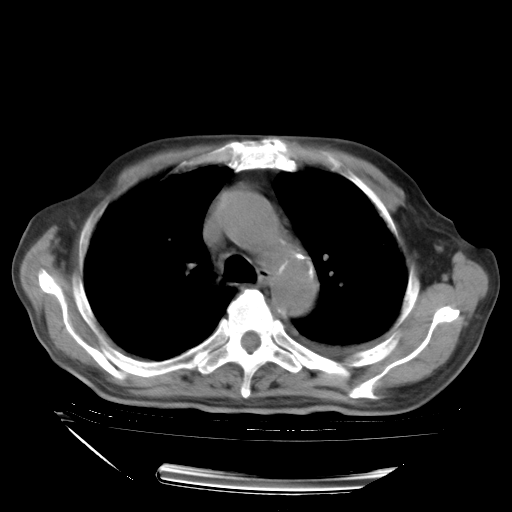

甲强龙80mg/日+抗结核治疗(异烟肼+利福霉素+乙胺丁醇)10天。复查肺部CT。

治疗10天肺部CT

补充下:5月9日胸部CT:似乎已见双下肺胸腔积液了,鉴于目前有下肢水肿,肝功示:白蛋白低,应注意多浆膜腔积液(漏出液可能大?),需注意!